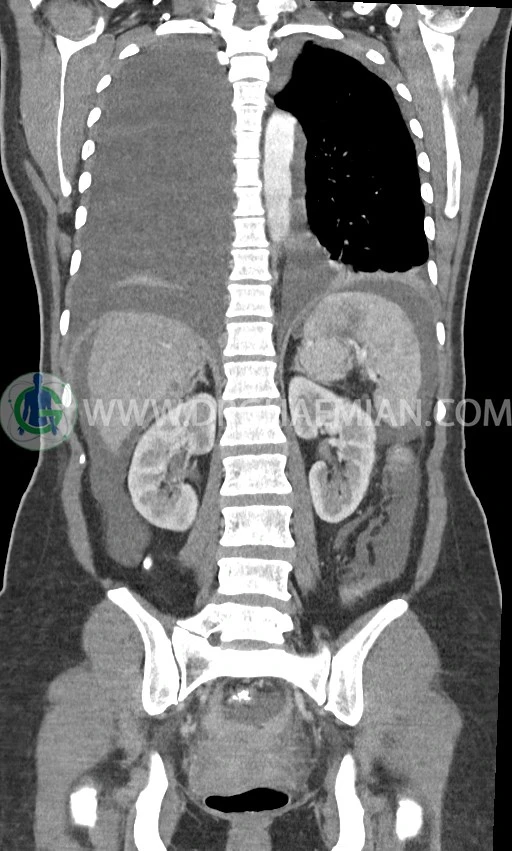

سی تی اسکن ریه با استفاده از اشعه ایکس تصاویر عرضی مقطعی از ریه و بالا تنه ایجاد می کند. در این کیس افیوژن پلور، لنفادنوپاتی، تخریب ریه سمت راست، توده پستان، آسیت و توده تخمدان دیده می شود.

در سی تی اسکن اسپیرال ریه، مدیاستن و شکم و لگن با کنتراست خوراکی و وریدی (مولتی دیدکتور 16 با مقاطع ظریف و بازسازی های ساژیتال و کرونال) :

ضایعه ای در کبد، کیسه صفرا، مجاری صفراوی، طحال، کلیه ها، پانکراس و آدرنالها مشهود نیست.

کلیه ها کنتراست را ترشح کرده اند و نمای سیستم پیلوکالیسیل و حالب دو طرف نرمال است .

اسیت قابل توجه در حفره شکم و لگن

توده سالید – سیستیک به ابعاد 40x60mm در تخمدان چپ و به ابعاد 20x40mm در تخمدان راست و

لنفادنوپاتی فراوان در اطراف آئورت و IVC با حداکثر SAD= 25mm در دیواره دو طرف حفره لگن با حداکثر SAD= 20mm

مشهود است.